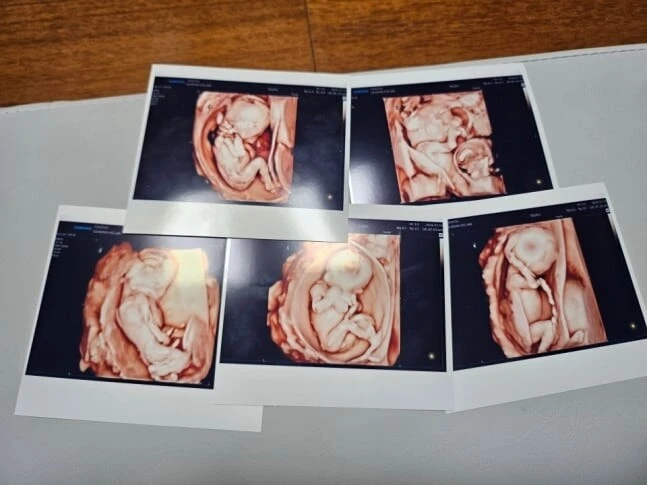

Thế giới y khoa vừa chứng kiến một sự kiện hy hữu khi người mẹ trẻ Dilire, chỉ mới 24 tuổi, đã viết nên một chương mới cho định nghĩa về sự kỳ diệu. Dù từng mang trong mình nỗi lo về hội chứng buồng trứng đa nang – một "rào cản" lớn đối với thiên chức làm mẹ – nhưng Dilire lại bất ngờ thụ thai tự nhiên. Mà không chỉ là một, cô đón nhận cùng lúc 5 mầm sống trong bụng, một trường hợp hiếm đến mức xác suất chỉ rơi vào khoảng 1 trên 60 triệu ca trên toàn cầu.

Tiếng khóc chào đời của 5 em bé – gồm một bé trai và bốn bé gái – vang lên trong sự vỡ òa của ê-kíp phẫu thuật. Những con số về cân nặng khiến nhiều người phải thắt lòng khi các bé chỉ nặng từ 870 gram đến hơn 1 kg, tức là chưa bằng một phần ba cân nặng của một đứa trẻ bình thường. Hình ảnh những cơ thể bé xíu, mong manh như những sợi nắng rạng đông đang nỗ lực hít thở đã tạo nên một làn sóng đồng cảm mạnh mẽ trên các nền tảng mạng xã hội.